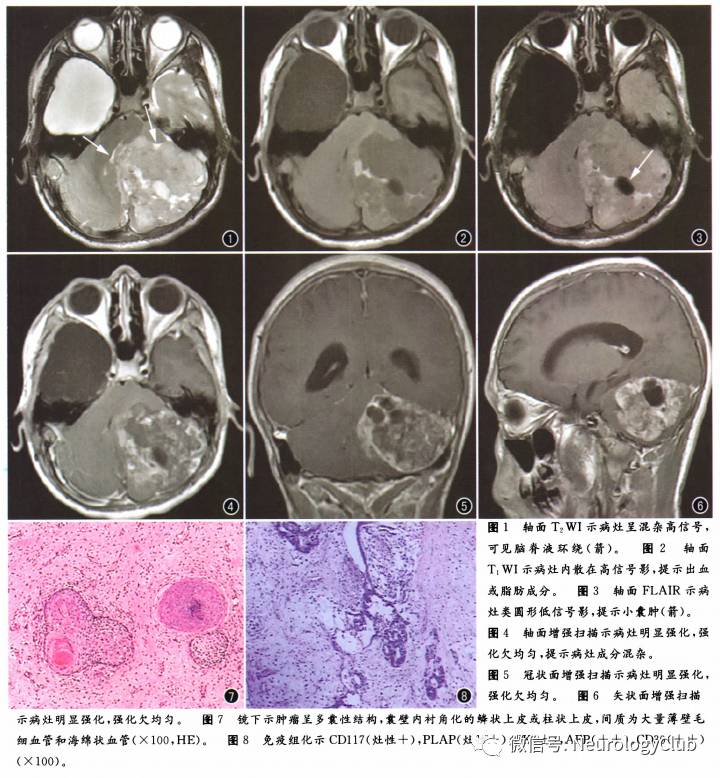

影像学检查:头颅MRI示左侧小脑半球及小脑蚓部可见一团块状异常信号影,边界尚清,大小约67mm×67mm。病灶T1Wl以稍低信号为主,其内间杂小片状高信号及更低信号,T2Wl呈不均匀高信号,其内可见多发小的囊变区,增强扫描病灶呈明显不均匀强化。相邻脑干及第四脑室明显受压向右移。右侧额颞部蛛网膜下腔增宽,见大片状长T1、长T2异常信号影,边界清,形状不规则,范围约55mm×50mm,增强扫描未见强化(图1-6)。

术后病理:病理组织学示肿瘤呈多囊性结构,囊壁内衬角化的鳞状上皮或柱状上皮,间质主要由大量薄壁毛细血管和海绵状血管构成,可见血栓形成伴机化,问质片灶性坏死。肿瘤均可见未成熟的上皮形成腺样或筛状结构,周边间质为幼稚的间叶组织(图7)。免疫组化:CD117(灶性+),PLAP(灶性+),CK(±),AFP(++),CD30(++),Vimentin(-),Villin(-);S100(灶性+),GFAP(灶性+,图8)。病理结果支持混合性生殖细胞肿瘤,恶性成份为胚胎癌(约占15%),成熟畸胎瘤约占85%。

本例患者病灶位于幕下,发病部位罕见,病理结果为胚胎癌与成熟畸胎瘤构成的混合性生殖细胞肿瘤,其中成熟畸胎瘤成分占85%,胚胎癌成分占15%,T1WI、T2WI病灶内可见条状、小片状高信号,提示病灶内可能包括脂肪成分、黏液蛋白以及出血的可能性。本侧肿块信号混杂,其内可见多发小的囊变区,增强扫描病灶呈明显不均匀强化,提示病灶成分多样,合并出血、坏死、囊变可能,恶性肿瘤可能性大。蒲苇等报道了1例发生于基底节区的混合性生殖细胞肿瘤(卵黄囊瘤和胚胎癌),表现为信号不均匀且其内有出血,CT呈稍高密度,DWI呈稍高信号,增强扫描呈不均匀强化。有研究认为CT平扫胚胎癌呈高密度,有时可见肿瘤钙化,可能与肿瘤恶性程度高、细胞密集有关。本例患者未行CT及DWI检测,故无法分析其CT及DWI表现。

混合性生殖细胞肿瘤MRI表现各异,并没有一定的特异性,信号特点取决于肿瘤内的成分,边界可清楚或不清楚,信号可均匀或不均匀,部分可见瘤周水肿,但增强扫描均呈明显均匀或不均匀强化。

混合性生殖细胞肿瘤仍具有一般生殖细胞瘤的影像学特点:由于细胞致密,CT平扫病灶内可见高密度影,由于病灶受限,DWI呈高信号。由于混合性生殖细胞瘤是由2种或2种以上生殖细胞肿瘤混合组成,所以CT平扫呈等/高混杂密度,MRI平扫呈混杂信号,病灶内T1WI常可见明显高信号,多为瘤内出血所致,少数含有成熟脂肪,增强扫描肿瘤也常呈混杂强化。